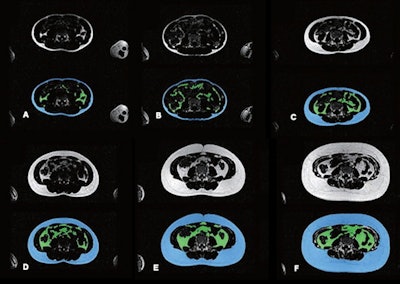

Researchers led by Tong Wu, MD, from Erasmus University Medical Center in Rotterdam found that their model could successfully perform segmentation for subcutaneous adipose tissue (SAT) and visceral adipose tissue (VAT) when assessing fat distribution on MRI, along with ties between such distribution and clinical outcomes.

They trained, validated, and tested the model, a competitive dense fully convolutional network (2D-CDFNet), on data from participants in the Generation R Study. This prospective population-based cohort study in Rotterdam included 2,989 children with an average age of 13.5 years. The participants underwent investigational whole-body Dixon MRI after reaching age 13 years, during the study's follow-up phase. The model was trained to segment abdominal SAT and VAT using Dixon-based MRI.

The researchers found that for the test dataset, the Dice similarity coefficient and volumetric similarity were 0.94 and 0.98 for SAT, respectively. For VAT, these measures were 0.85 and 0.92, respectively. These results indicate that the model demonstrated strong quantitative performance.